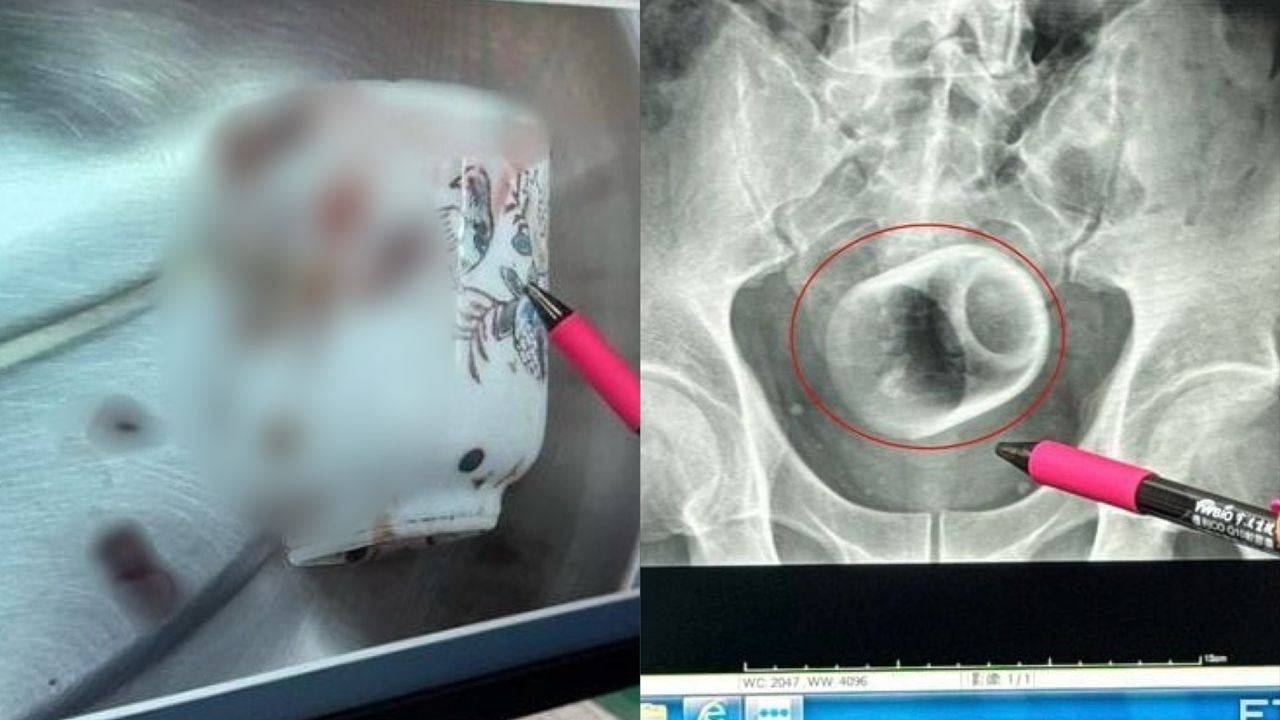

Hasil ujian X-ray mendedahkan bahawa cawan seramik berdiameter 6 sentimeter dan panjang 8 sentimeter tersekat di dalam duburnya.

Doktor-doktor cuba menarik keluar cawan itu dengan penyepit tetapi gagal akibat permukaan licin.

Mereka terpaksa melakukan pembedahan kecemasan di bahagian perut bagi mengeluarkan cawan itu dengan selamat.